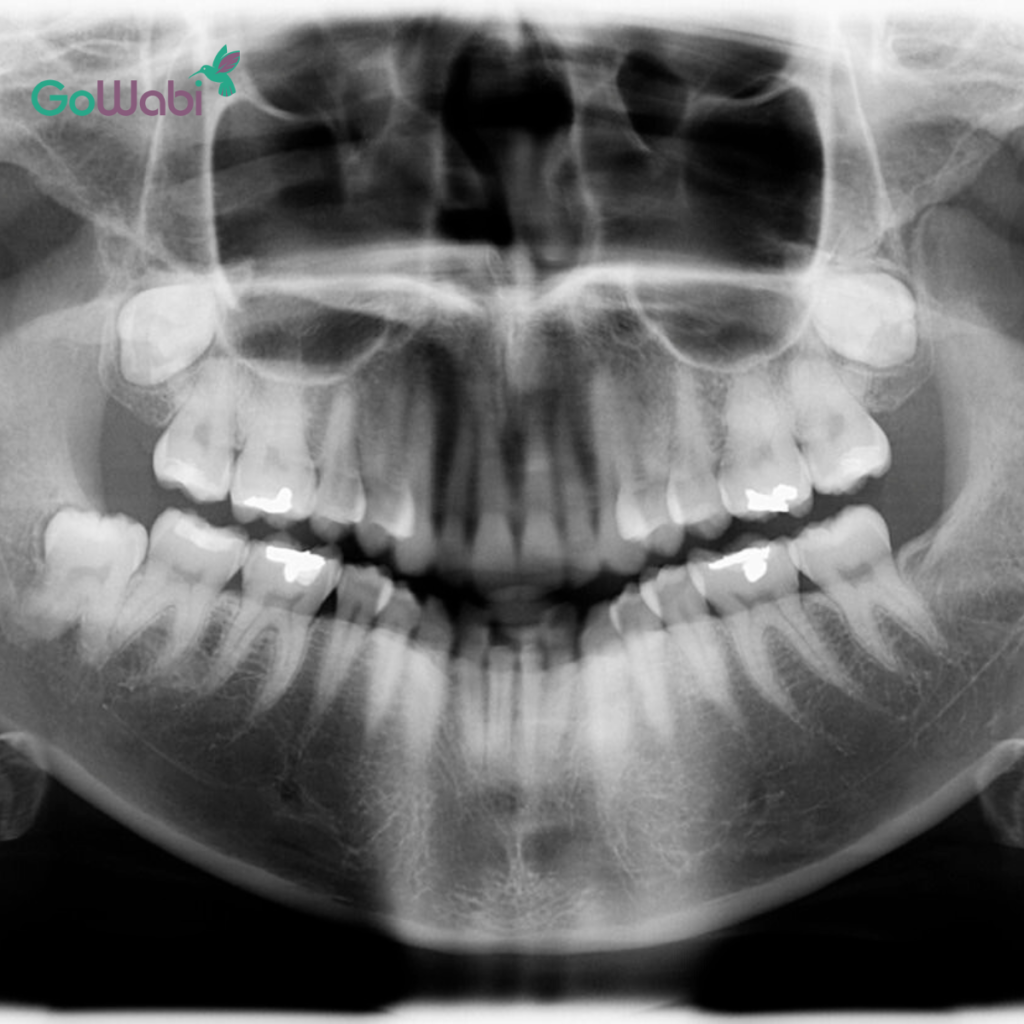

1. ปรึกษาและตรวจประเมินฟัน

ฝ้ายเริ่มจากการจองคิวเข้าปรึกษากับ DCA Dental Clinic สาขาสุขุมวิท 49 คุณหมอจะทำการตรวจเช็กฟันของเราอย่างละเอียด ว่าปัญหาฟันของเราสามารถแก้ไขด้วย Dr Clear Aligners ได้หรือไม่ ซึ่งปัญหาที่ฝ้ายเป็นกังวลก็คือ ฟันซ้อน ฟันเก ค่ะ

หลังจากนั้นก็ทำการสแกนฟันแบบ 3D เพื่อดูโครงสร้างฟันของเราผ่านคอมพิวเตอร์ และทำแผนการรักษาให้เห็นล่วงหน้าว่าฟันของเราจะค่อย ๆ ขยับไปตำแหน่งไหนบ้าง